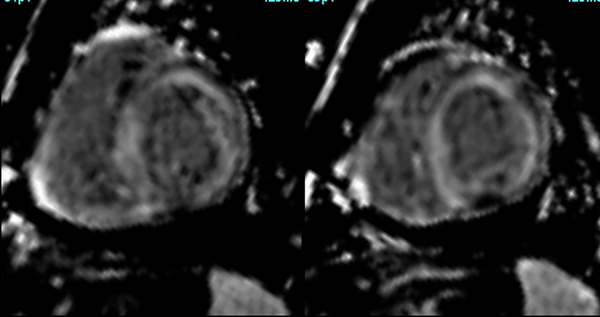

Cardiac MRI is a useful tool to diagnose amyloidosis. T1 mapping has become a mainstay, both native and ECV measurements. ECV measurement can now help quantify the amyloidosis burden and may help guide treatment based on how the ECV responds to specific treatment measures.